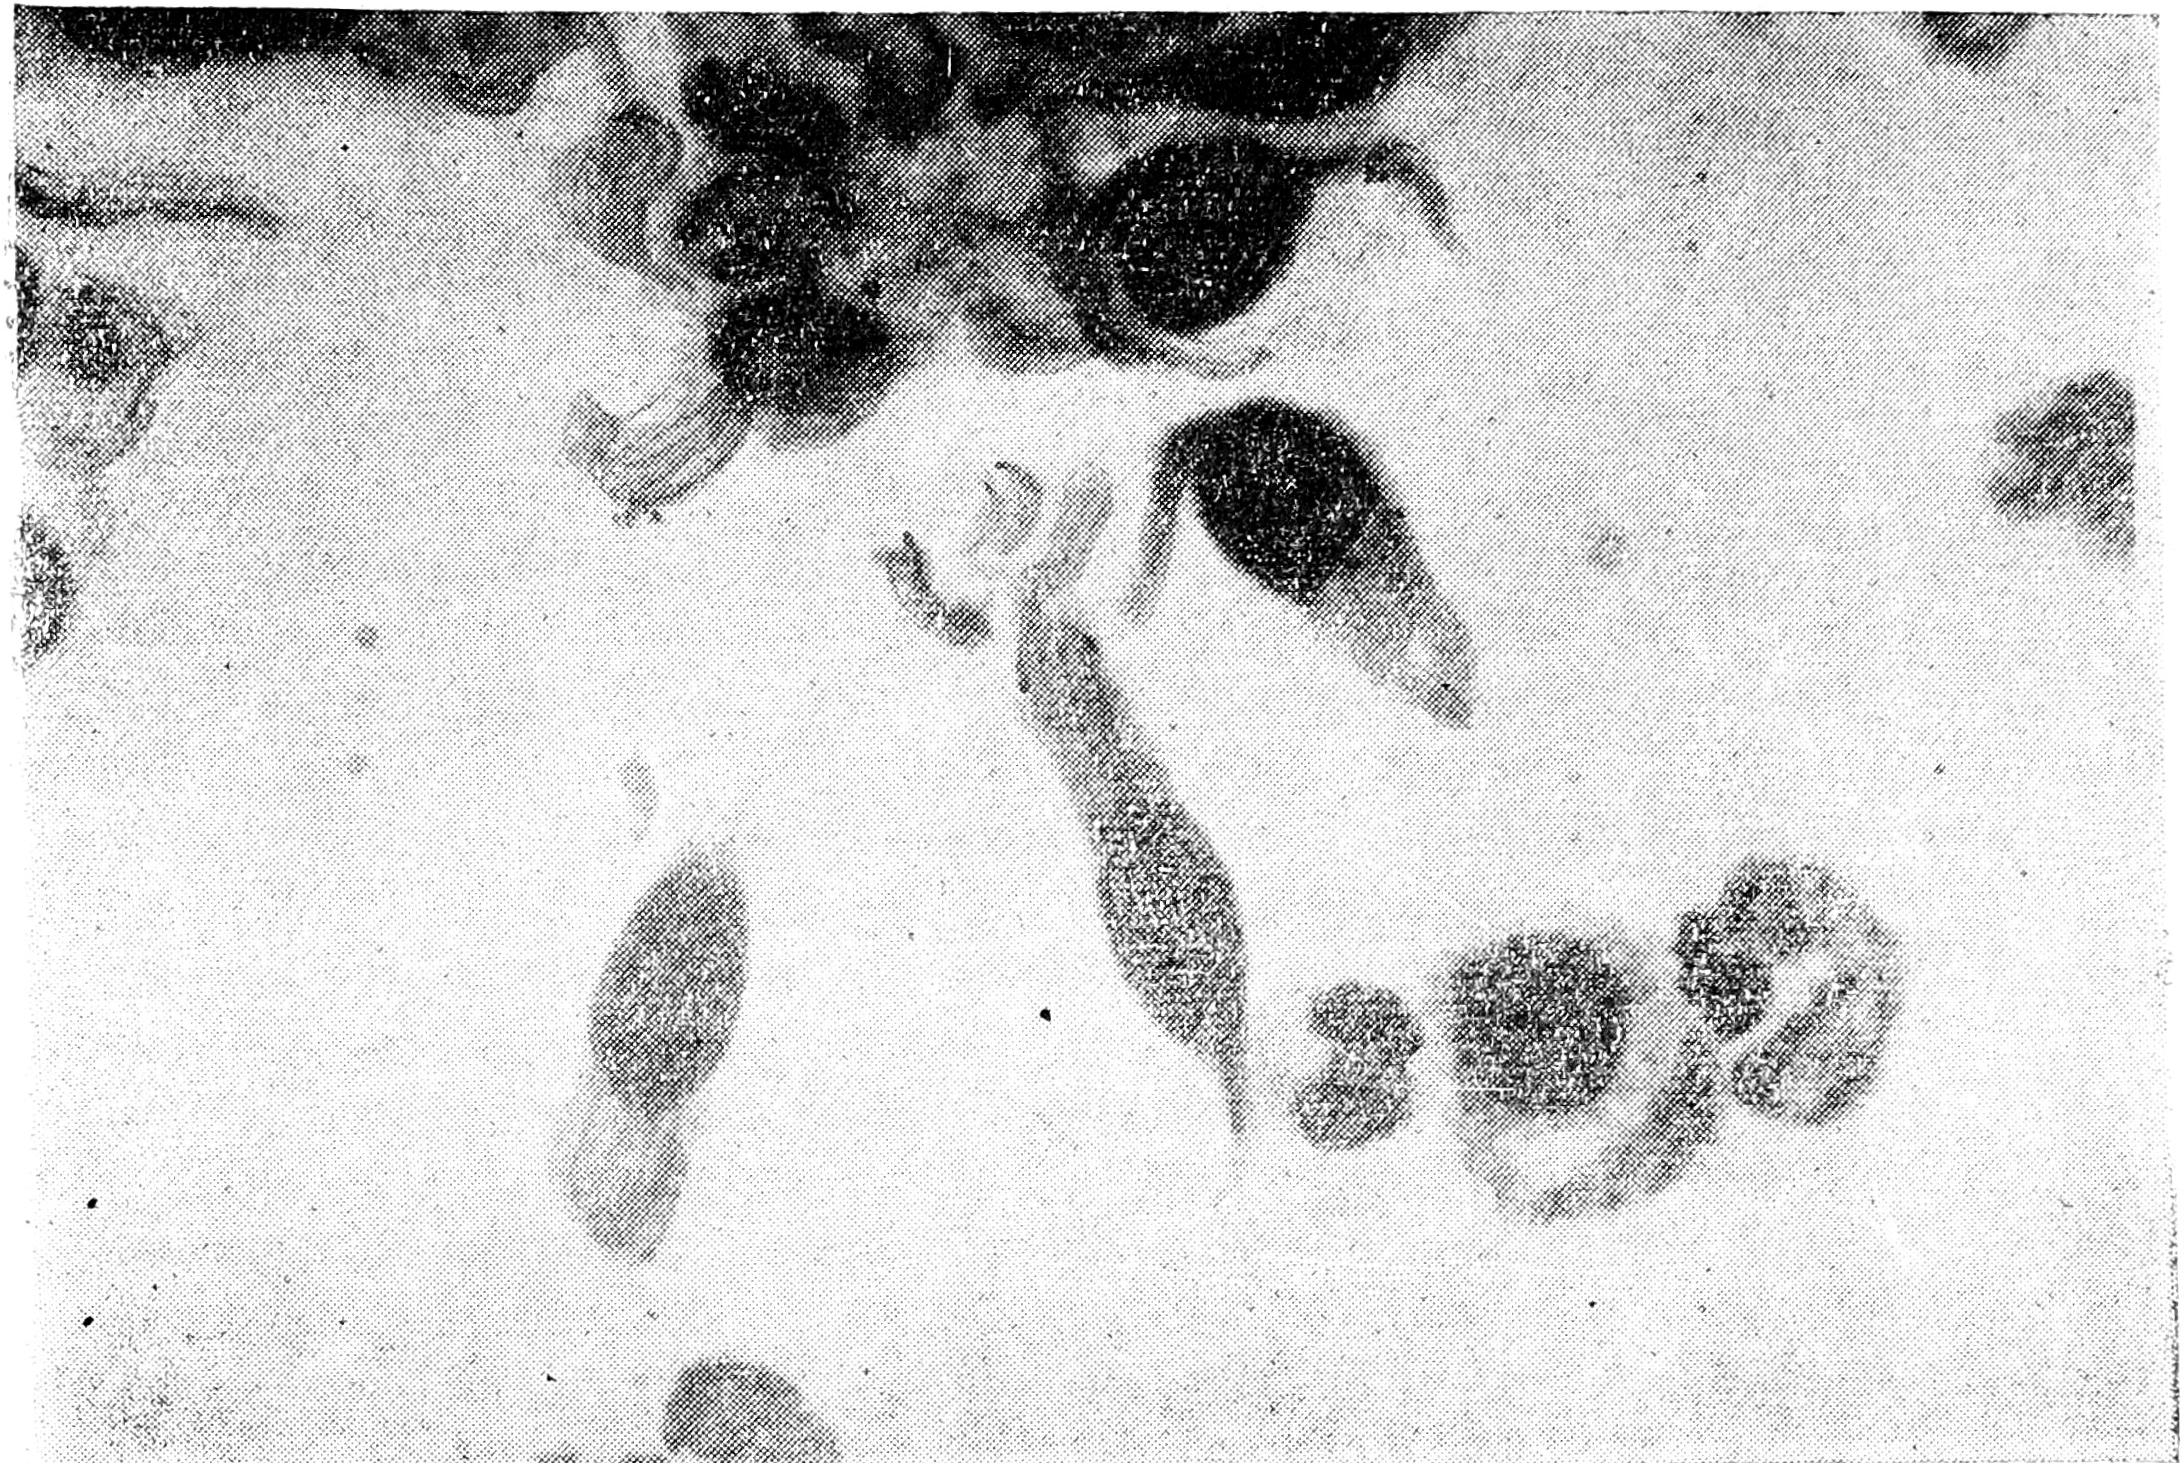

Форма этих частиц, изученная в электронном микроскопе (рис. 1 и 2), представляется чаще круглой, а у вируса А — эллипсоидной или бобовидной. Кроме того, имеются палочковидные и нитевидные формы различной величины, встречающиеся особенно часто в аллантоисной жидкости зараженных куриных эмбрионов. Возможна фрагментация палочковидных форм на круглые. Хойл предполагает, что продолговатые формы состоят из липоидной оболочки, заключающей в себе круглые образования.

Рис. 1. Вирус гриппа. Электронная микроскопия, увеличение в 40000 раз (по Т. Риверсу).

Рис. 2. Вирус гриппа. Электронная микроскопия, увеличение в 11,333 раза (по Г. Маковер).